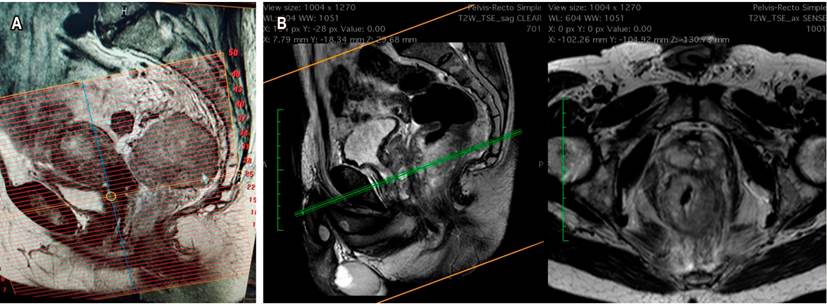

Si se tomó la decisión de neoadyuvancia por CRM positiva, o por riesgo de estarlo, la reestadificación se hace con una RM simple adicional, con evaluación de las secuencias de T2, de restricción a la difusión y el índice de regresión tumoral. Esta evaluación se hará dependiendo del tipo de neoadyuvancia que se realice: si es convencional, a las 6 semanas de haber terminado la radioterapia, pero si fue TNT (nuevo concepto), la medición se hará al terminar la quimioterapia de consolidación. Una de las dificultades frecuentemente encontradas en el estudio es que habitualmente se solicita como RM de pelvis. Si no se especifica y se solicita la RM con protocolo de recto, el técnico hará la alineación y la reconstrucción de las imágenes en forma inadecuada, y estas no serán perpendiculares al eje del recto y el tumor, lo que no permite evaluar correctamente la subclasificación del T. Es recomendable establecer, con su grupo de trabajo, la revisión de la técnica de reconstrucción de imágenes (Figura 5)14,15.